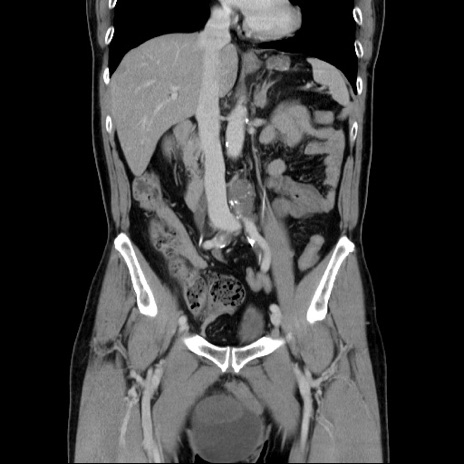

症例34(冠状断像)

【症例】60歳代 男性

【主訴】右鼠径部膨隆

【現病歴】1年程前より右鼠径部膨隆あり。自己にて還納可能だったため放置していた。3時間前より右鼠径部の脱出を認め、還納困難となり受診。

【既往歴】高血圧

【身体所見】右鼠径部に小児頭大の膨隆あり。弾性硬であり、用手還納は困難。左鼠径部にも膨隆を認める。脱出はなし。